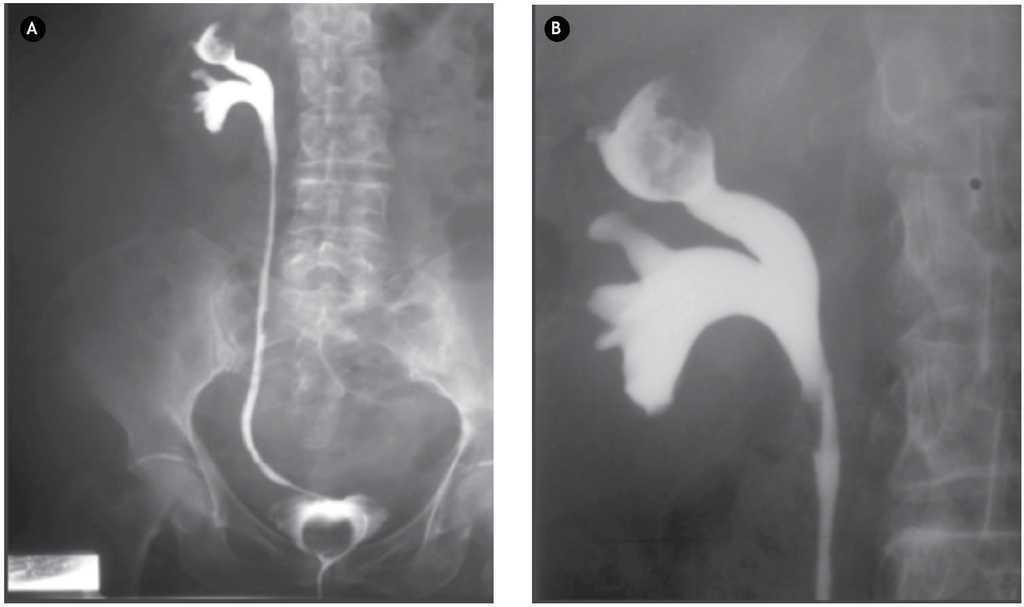

El pielograma fue concluyente con presencia de defecto de llenado en cáliz superior de riñón derecho, con imagen característica en "manzana mordida" (Figura 2). El reporte de la citología fue negativo.

Figura 2. A) y B) Pielograma ascendente. Con imagen característica de "manzana mordida" en cáliz superior.